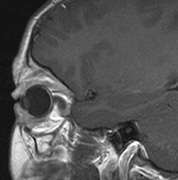

Intracranial leptomeningeal capillary vascular malformation (Figs. 21 and 22) is associated with seizures and contralateral neuromuscular weakness. Central nervous system involvement correlates highly with ipsilateral involvement of the V1 dermatome by a PWS.208,218

Fig. 21. Sturge-Weber syndrome: leptomeningeal vascular malformation.